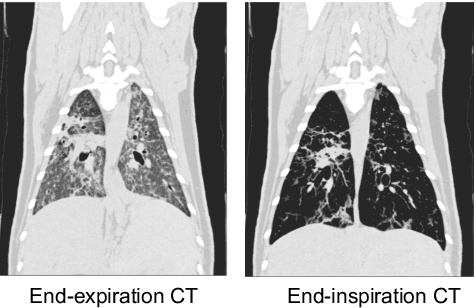

Abstract:Chest computed tomography (CT) at inspiration is often complemented by an expiratory CT for identifying peripheral airways disease in the form of air trapping. Additionally, co-registered inspiratory-expiratory volumes are used to derive several clinically relevant measures of local lung function. Acquiring CT at different volumes, however, increases radiation dosage, acquisition time, and may not be achievable due to various complications, limiting the utility of registration-based measures, To address this, we propose Lung2Lung - a style-based generative adversarial approach for translating CT images from end-inspiratory to end-expiratory volume. Lung2Lung addresses several limitations of the traditional generative models including slicewise discontinuities, limited size of generated volumes, and their inability to model neural style at a volumetric level. We introduce multiview perceptual similarity (MEAL) to capture neural styles in 3D. To incorporate global information into the training process and refine the output of our model, we also propose self-ensembling (SE). Lung2Lung, with MEAL and SE, is able to generate large 3D volumes of size 320 x 320 x 320 that are validated using a diverse cohort of 1500 subjects with varying disease severity. The model shows superior performance against several state-of-the-art 2D and 3D generative models with a peak-signal-to-noise ratio of 24.53 dB and structural similarity of 0.904. Clinical validation shows that the synthetic volumes can be used to reliably extract several clinical endpoints of chronic obstructive pulmonary disease.